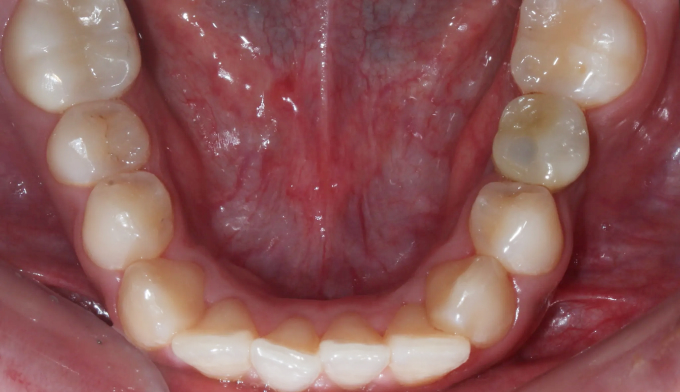

돌출입과 불규칙한 앞니를 가지고 있습니다. 그리고 아래쪽에 ‘임플란트’가 있습니다.

임플란트는 뼈와 강력히 결합되어 있기 때문에 교정치료로 절대 움직일 수 없습니다. 따라서 해당 부위는 절대 교정치료로 움직일 수 없다는 제한점이 있는 상태에서 교정치료를 진행하게 되었습니다.

돌출입을 해소하고 앞니를 가지런하게 만들기 위한 공간을 만드는 과정중에는 저 임플란트를 꼭 제거해야 했으나, 최대한 발치 없이 교정을 진행하였습니다.

후방이동이 불가하므로 악궁확장을 통하여 공간확보를 시도하였고, 동시에 돌출감도 해소되었습니다.

최종적으로 임플란트의 존재때문에 중심선을 맞추지는 못했으나 환자분은 너무 만족해하셨습니다.